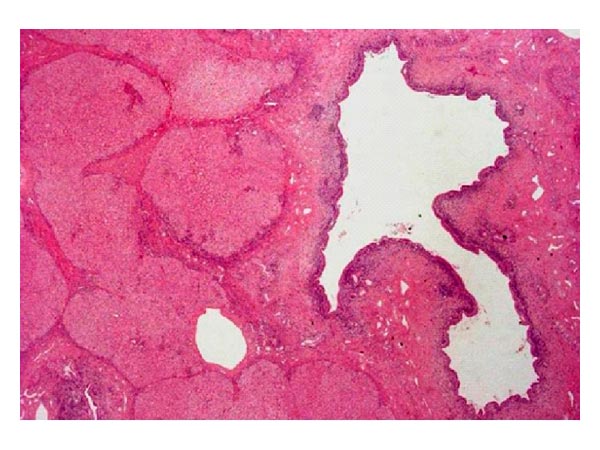

Болезнь Кароли — это редкое генетически обусловленное заболевание, при котором происходит расширение внутрипеченочных желчных протоков. Патология проявляется интенсивными болями в области правого подреберья, желтухой, изменениями цвета мочи и кала.

| Название заболевания | Болезнь Кароли (Caroli disease) | Редкое врожденное заболевание, характеризующееся кистозным расширением внутрипеченочных желчных протоков. |

Аномалии желчных протоков: Основной признак болезни Кароли — это аномальное расширение желчных протоков, что может привести к различным осложнениям, таким как инфекции, желчнокаменная болезнь и даже цирроз печени. Эти изменения могут быть визуализированы с помощью ультразвукового исследования или магнитно-резонансной холангиографии.